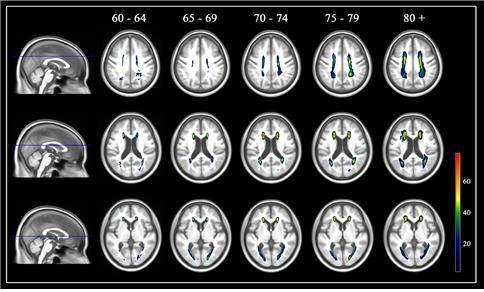

이 확률지도를 이용하면 대뇌 백질고강도신호가 60~64세, 65~69세, 70~74세, 75~79세, 80세 이상의 다섯 개 연령군 중 어디에 해당하는지를 판정할 수 있다. 이렇게 결정된 백질고강도신호 연령은 자신의 실제 나이와 동일할 수도 있고, 실제 나이보다 적거나 많을 수도 있다.

| ▲그림1. 연령별 한국 노인 백질고강도신호 확률지도 [분당서울대병원 제공] |